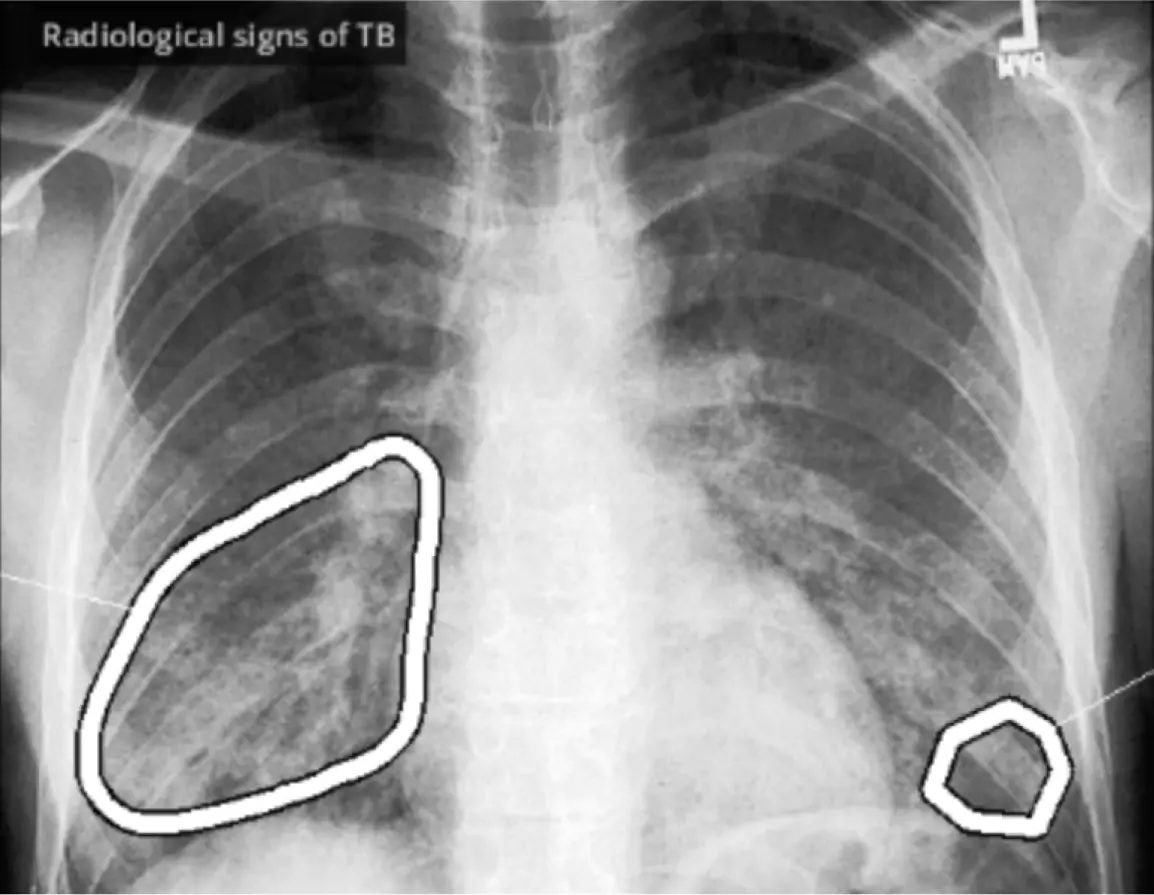

WHO evaluated AI-based TB screening and triage tool. A complete end-to-end platform for screening programs & case management.